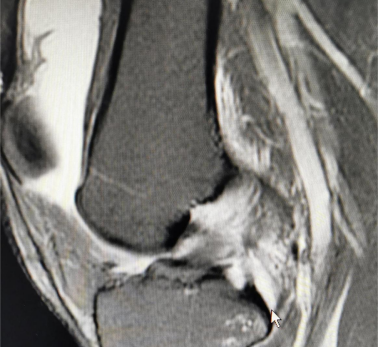

59岁姚阿姨操劳半辈子,因为膝关节反复疼痛而到处求医。近日,慕名来我院就诊,骨科姚磊主任详细询问病史、查看检查资料,考虑半月板三度损伤,做了关节镜下半月板修复治疗,术后第二天即可下地活动,术后第三天就康复出院。

膝关节内的软骨结构、滑膜、半月板、韧带和关节面的损坏在X线片上往往难以发现,但在关节镜下却一目了然。原则上,任何膝关节内的病变都是膝关节镜的手术适应症。